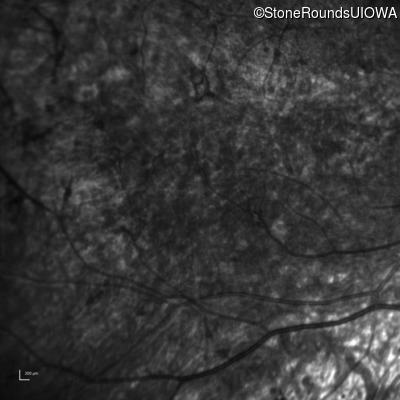

Infrared Fundus Photograph - Left - 5/180

Exemplar